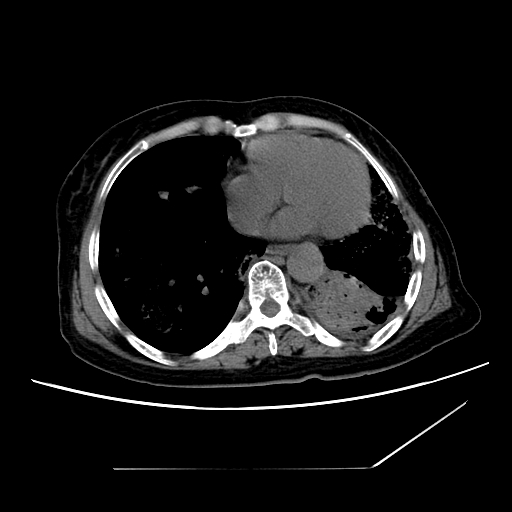

标题: CT25393:病人45岁,咳嗽,吐黄痰带血丝,发热,胸闷月余 [打印本页]

标题: CT25393:病人45岁,咳嗽,吐黄痰带血丝,发热,胸闷月余

1、左肺中央型肺癌并双肺弥漫性转移   2、双肺部感染    3、肺大泡     4、左侧胸腔积液

双侧肺弥漫性病变,可见“空泡征”及“蜂窝征”,考虑肺泡癌可能性大,左侧胸腔积液,考虑胸膜受累可能!

考虑肺泡癌,建议排除感染。

考虑肺泡癌

1)不排除肺泡癌可能。2)左侧胸腔积液。